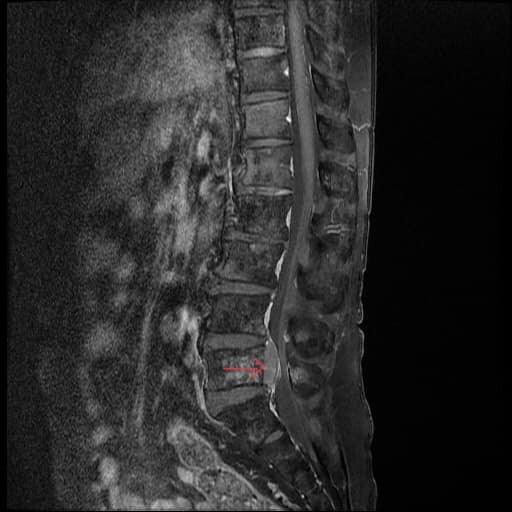

![]() |

| Hình ảnh khối u chèn ép tủy sống trên phim MRI của bệnh nhân. Ảnh: BVCC |

Sau khi nhập viện điều trị, bệnh nhân được các bác sỹ thăm khám và chỉ định chụp MRI cột sống phát hiện khối u tủy L5 phát triển từ khối di căn cột sống gây choán chỗ, hẹp nặng ống sống và chèn ép các cấu trúc thần kinh.